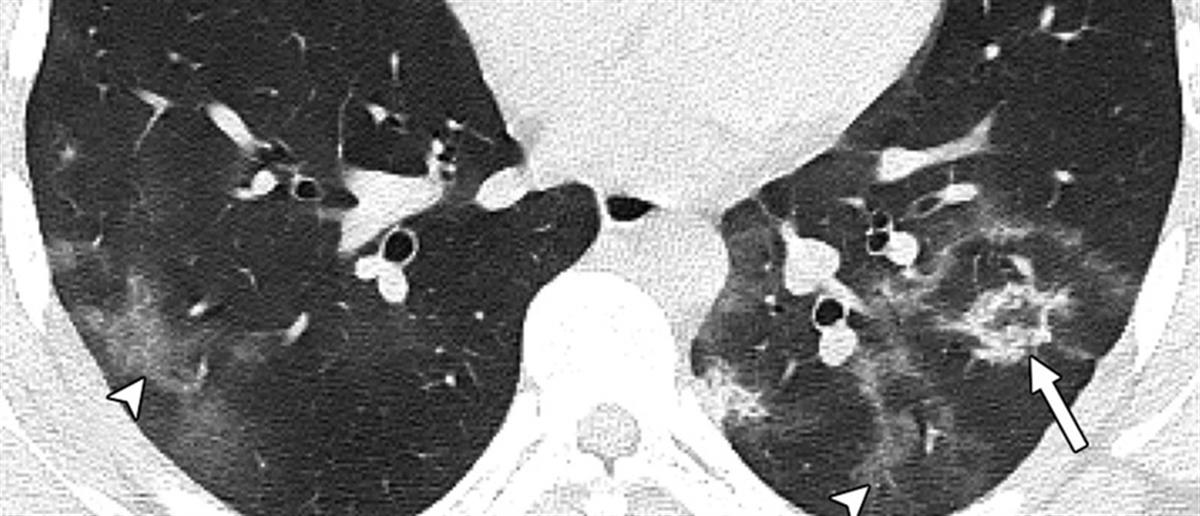

Το μήνυμα συνοδεύεται από αξονικές τομογραφίες νέων, κάτω των 18 ετών, που νόσησαν και δείχνουν τις σοβαρές βλάβες που υπέστησαν στους πνεύμονες.

«Μία εικόνα χίλιες λέξεις.

Αξονικές τομογραφίες νέων κάτω από 18 έτη με COVID-19 (18 ετών, 15 ετών, 14 ετών και 8 ετών). Κανένας ασθενής δεν είχε υποκείμενα νοσήματα ή ανοσοκαταστολή. Οι ασθενείς δεν χρειάστηκαν συμπληρωματικό οξυγόνο, διασωλήνωση ή ΜΕΘ. Πρόκειται για απλά-κοινά περιστατικά COVID-19.

Ωστόσο έχουν πολύ “εντυπωσιακές” βλάβες και είναι άγνωστο τι θα προκαλέσουν αυτές οι βλάβες σε βάθος χρόνου.